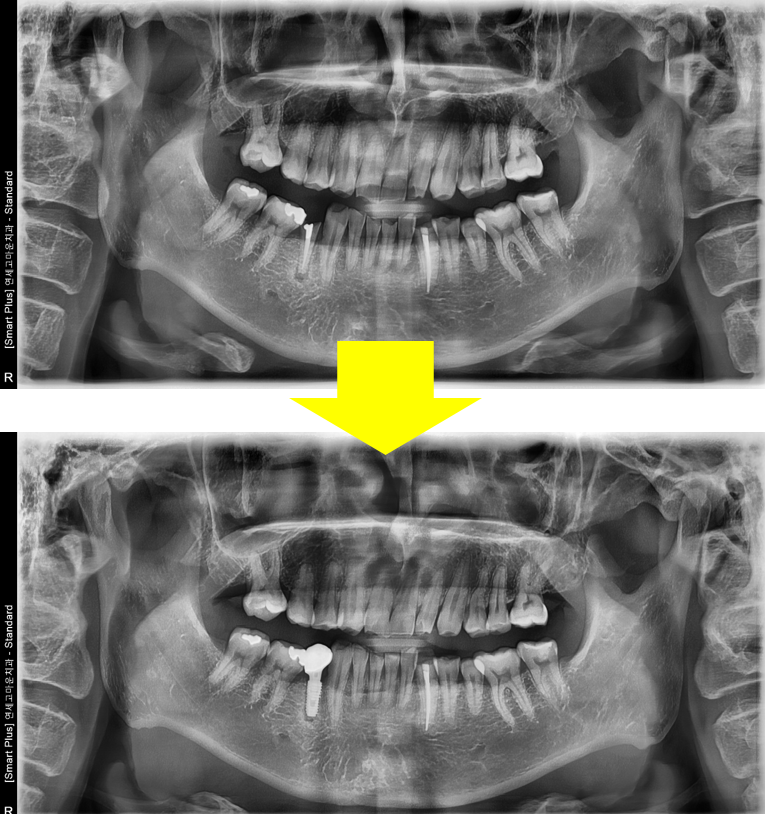

임플란트는 자연치를 대체할 수 있는 가장 좋은 술식입니다. 높은 성공률을 위해서는 많은 임상 경험과 수술 후 관리가 반드시 필요합니다.

연세고마운치과는 풍부한 임상경력과 첨단 술식으로 안정성이 검증된 재료만 사용합니다. 첨단 장비를 사용하여 정밀하게 진단하고, 엄격하게 멸균 소독된 기구를 사용하며, 임플란트 식립에서 끝나지 않고 철저한 사후관리까지 책임집니다.